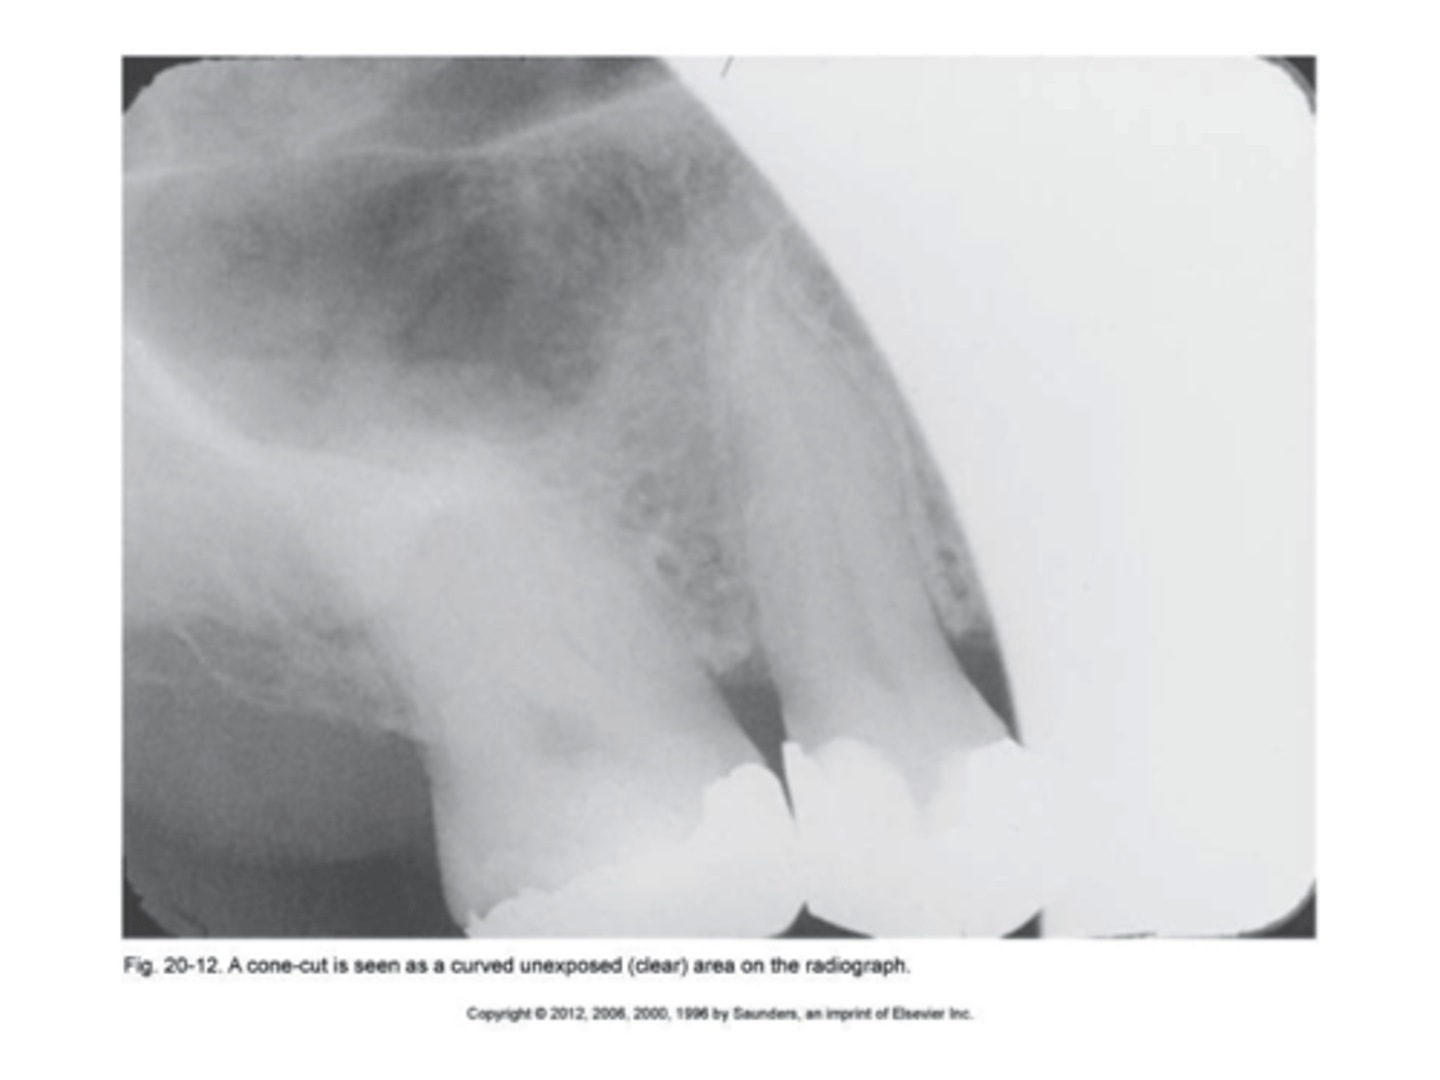

cone cut with beam alignment device (PA)

clear or white unexposed area

PID was not properly aligned with the beam alignment device

cone cut without beam alignment device (PA)

bisecting technique when a beam alignment device is not used

a clear or white unexposed area

PID was not directed at the center of the receptor

make sure PID is directed over the center of the receptor